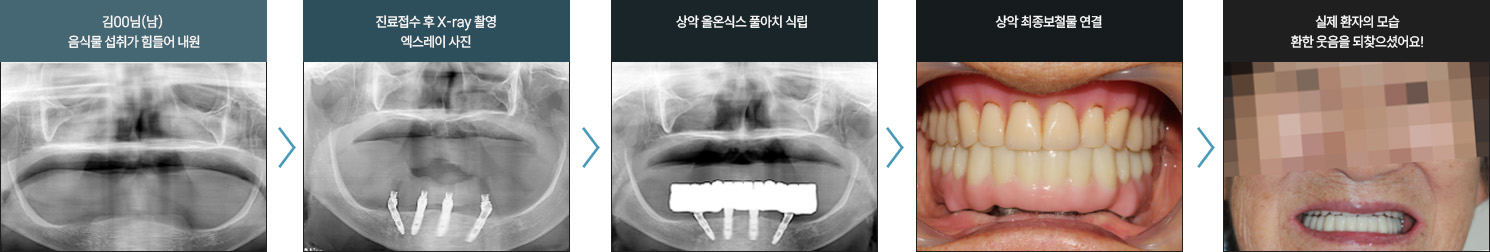

I      올온식스 풀아치 임플란트 사례      I

치료 기간 : 2021.05.08 ~ 2021.11.19

치료 기간 : 2022.05.17 ~ 2022.12.05

전북 외곽 지역에서 먼 걸음 해주신 환자분입니다

치아 손실로 오랜 기간 불편함을 겪으셨고, 잇몸뼈 흡수가 진행된 상태였습니다.

정밀 진단을 통해 잔존 치조골을 평가하고, 풀아치 임플란트 계획을 세워 단계적으로 치료를 진행했습니다.